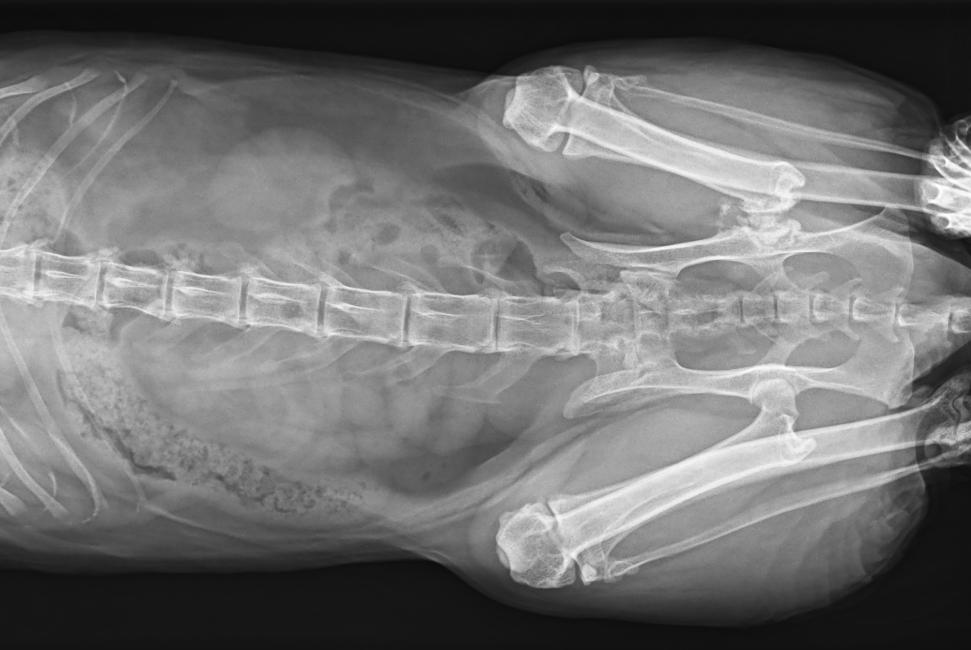

● 17*17大尺寸平板探測器,獲得高質(zhì)量圖像

● 優(yōu)異的空間分辨率及信噪比,提升圖像質(zhì)量

● 采用線噪聲消除技術(shù),使成像質(zhì)量提升40%

● 智能高效的圖像處理軟件,大幅提升圖像質(zhì)量

● 可浮動床面設(shè)計,滿足大部分中小型寵物檢查